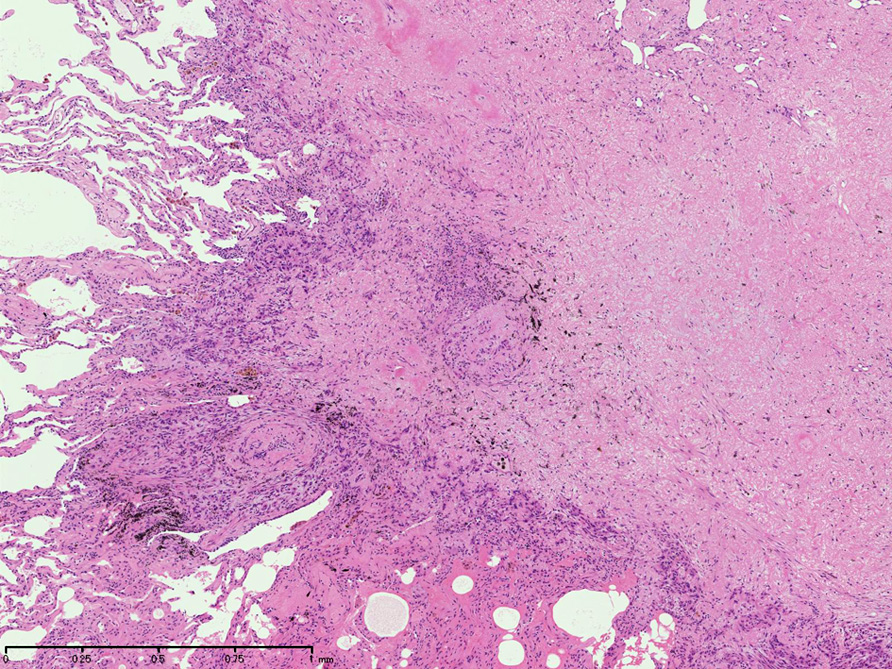

直径5-6mmの, 中央に弾性線維をふくむfibrous noduleがあり, 腫瘍細胞は結節の辺縁部に沿って認められる。

hyperchromaticな類円ないし多角の核で好酸性の広めの細胞質をもつ上皮様細胞が増殖している。右図では血管内を占拠するように腫瘍細胞が認められる。

左図:腺腔様の裂隙が胞巣内にみられ, 凍結標本だと腺癌との区別がむずかしい。